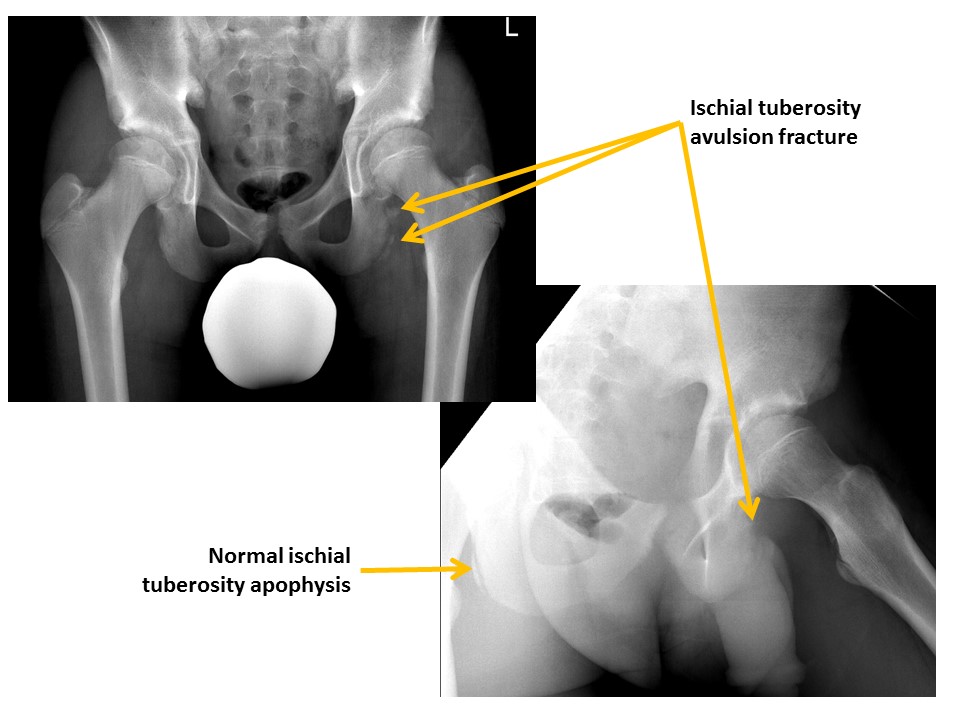

There are avulsion fractures at the ischial tuberosities. [Yes/No]